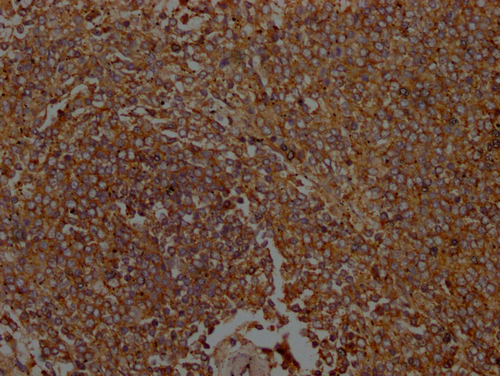

IHC image of CSB-PA010951LA01HU diluted at 1:100 and staining in paraffin-embedded Human spleen tissue performed on a Leica BondTM system. After dewaxing and hydration, antigen retrieval was mediated by high pressure in a citrate buffer (pH 6.0). Section was blocked with 10% normal goat serum 30min at RT. Then primary antibody (1% BSA) was incubated at 4°C overnight. The primary is detected by a Goat anti-rabbit polymer IgG labeled by HRP and visualized using 0.05% DAB.